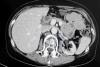

Radiațiile de la CT, la fel de cancerigene ca alcoolul | Galerie Foto | Imagine 2